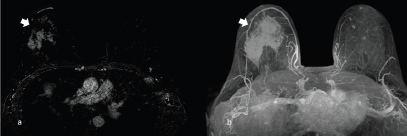

Magnetic resonance imaging using T2-weighted images may show granulocytic sarcoma as ill-defined, heterogeneous, hyperintense masses relative to breast parenchyma, and hypointense on T1 images (Figure 5), inhomogeneous enhancement (Figure 6) on gadolinium administration and restricted diffusion (Figure 7).

Figure 6. A 63-year-old patient presenting a right unilateral breast mass subsequently identified as a MS. (a) Inhomogeneous enhancement on gadolinium administration (arrow) and (b): the appearance of the mass enhancement (arrow) in the maximum intensity projection.

MS can also be found fortuitously during CT or PET examination in oncologic patients ([14–16]; Figure 8).

The typical appearance is of an irregular breast mass with inhomogeneous contrast enhancement and glucose uptake. On occasion, patients with MS of the breast can present other soft tissue localisation, such as the kidney (Figure 9).The histopathological diagnosis is challenging especially for the difficulties encountered distinguishing MS from lymphoma (Figures 10–12).

Figure 8. A 50-year-old patient presenting a right unilateral, incidental finding of breast mass subsequently demonstrated to be a MS. (a): Irregular breast mass on the computed tomography exam, showing inhomogeneous contrast enhancement (arrow). (b):The abnormal glucose uptake in PET examination (arrow).